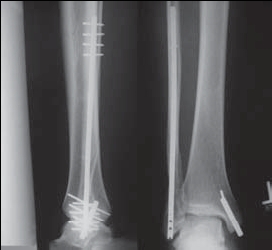

Если и оперировать, то, наверное, целесообразно бы поставить IP-XSL (long nail). И косметический дефект минимальный, и нагрузка сразу и удалять нет особой необходимости.

У нас бы не оперировали. Кость неопорная, пусть даже и псевдоартроз сформируется, на осевую нагрузку это не повлияет. С другой стороны, дувушка спортсменка, реабилитация должна быть как можно скорее.